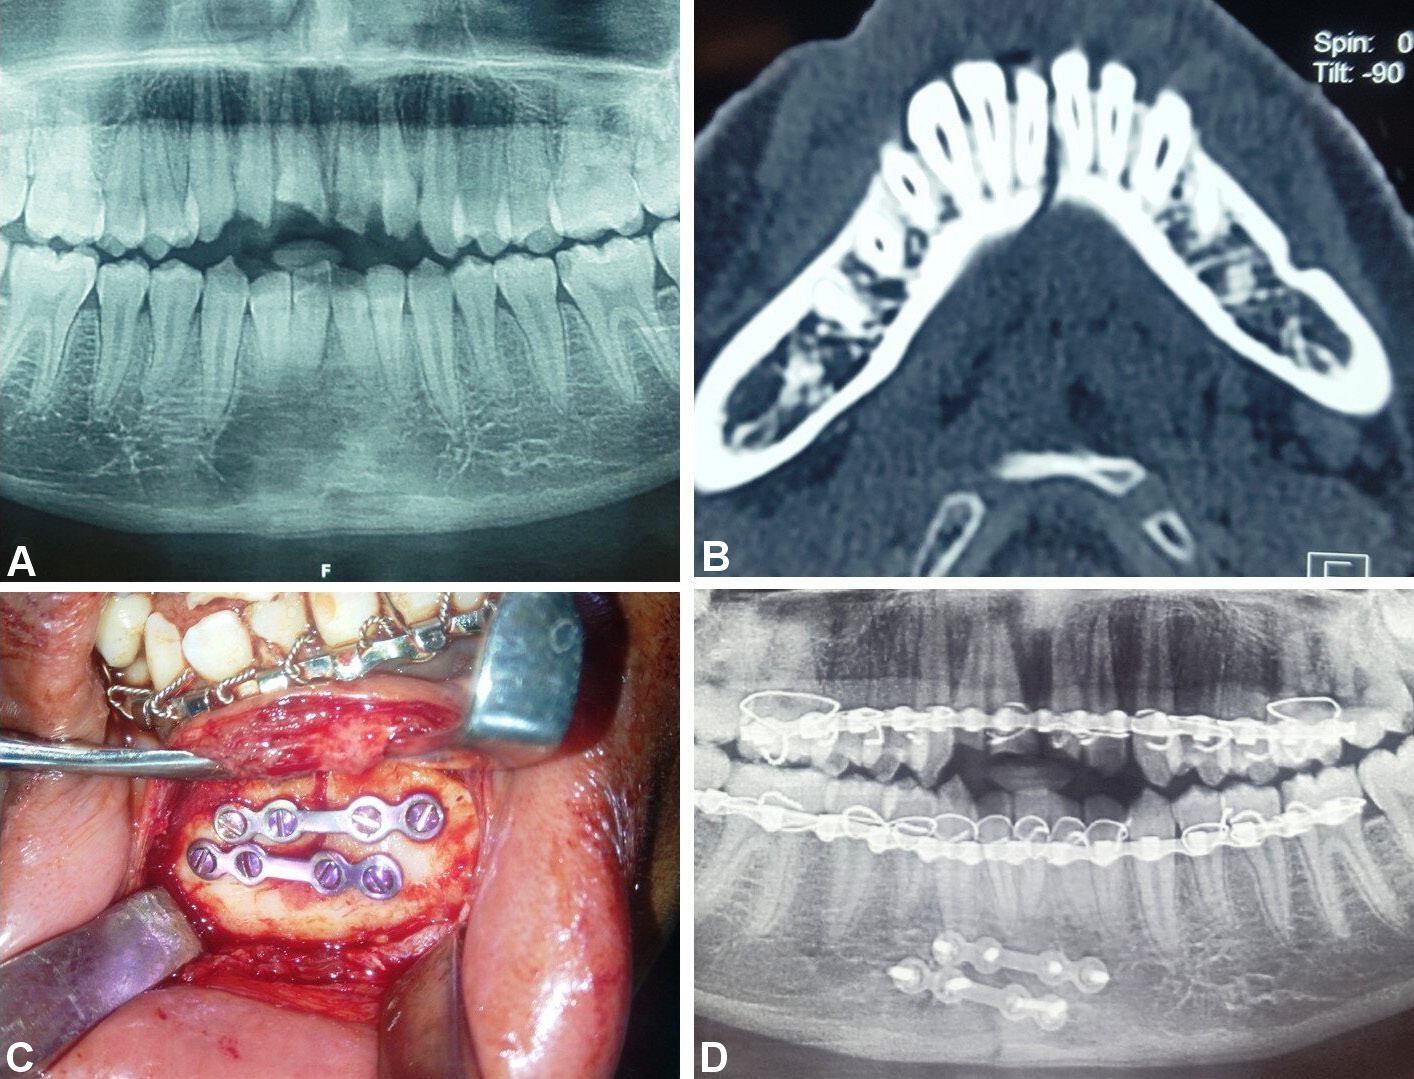

In group B, fixation was conducted using 2 titanium miniplates (2.0-mm, 4-hole design with a gap) and 8 miniscrews (2 mm × 8 mm and 2 mm × 10 mm), which were positioned subapically and at the inferior border of the mandible according to Champy’s lines of osteosynthesis (Figure 5, Figure 6, Figure 7).